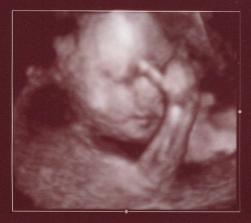

Bocian dorazil o viac ako mesiac skor (ukecal som ho, uz ma to tam nebavilo...) a tak som sa miesto 15.5. narodil 11.4. Mal som vsetko co som mal mat /2790g a 48cm pri porode/ a tak po ohriati sa par dni v inkubatore a zltacke sme prchali z porodnice s pripisanou vahou po 12-tich dnoch - uz sme tam nemohli dalej vydrzat! :o) Nastastie jedna zlata sestricka nam pomohla sa odtial dostat za co jej velmi pekne dakujeme! Dalsie fotky su v mojom druhom albume...